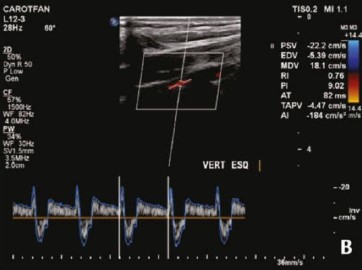

Foi realizado ecodoppler de artérias carótidas e vertebrais, como mostra a imagem a seguir.

Assinale a alternativa que corresponde ao diagnóstico correto para a paciente nesse caso.